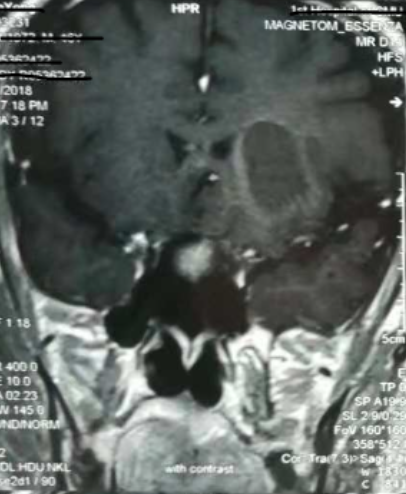

術(shù)前CT:血腫已經(jīng)液化,但仍有占位效應(yīng)

增強核磁提示:血腫液化周邊增強